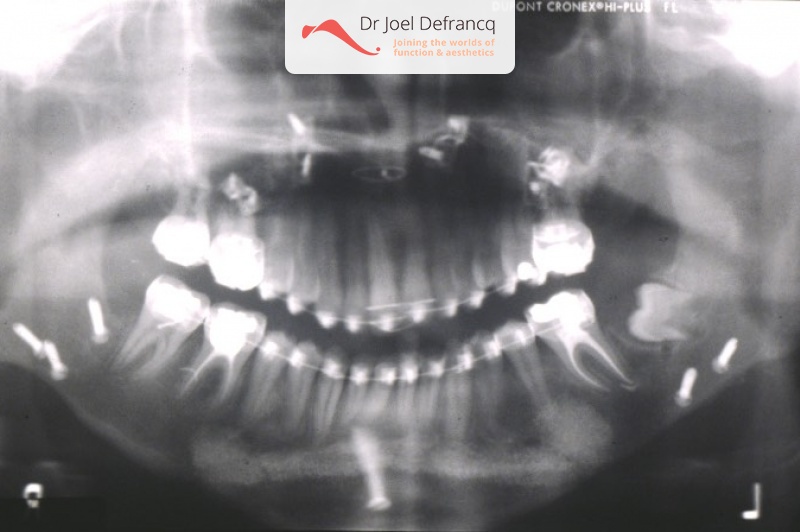

Danice: too big upper jaw.

Diagnose van het gezicht

- Te kleine onderkaak (Overbeet)

- Te grote bovenkaak

- Te lange bovenkaak

Kaakchirurgie

- Verlenging onderkaak (BSSO)

- Naar achter plaatsen bovenkaak (Le Fort I)

- Vertikale verkorting bovenkaak (Le Fort I)

- Kinchirurgie